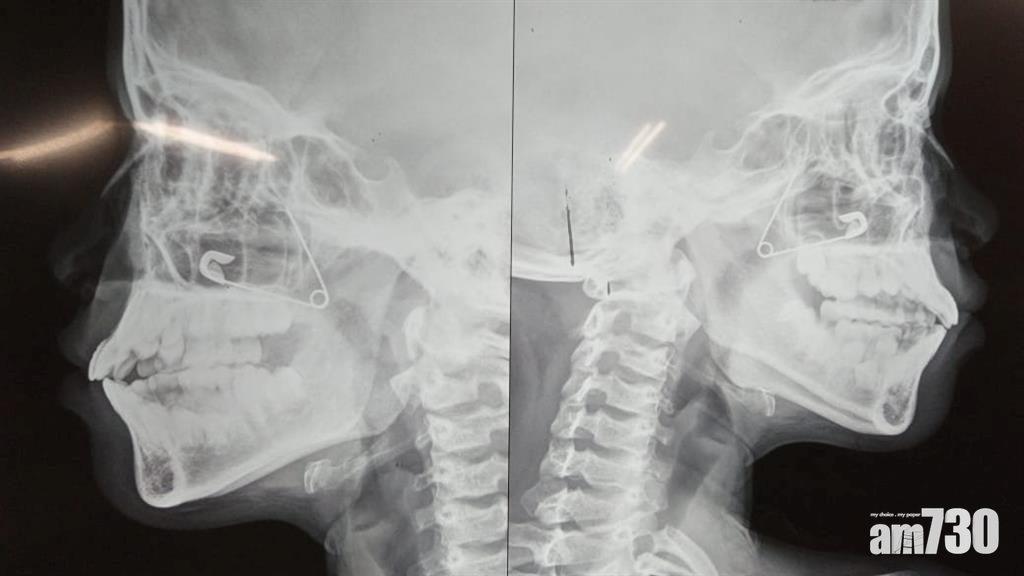

X光檢查顯示,扣針呈打開狀,卡在萊特鼻孔深處。(互聯網)

印度西孟加拉邦10歲女童萊特(Moumita Let)竟用扣針「撩鼻屎」,未料扣針突然打開,卡在鼻孔深處,令她鼻血長流兼劇痛難忍。經X光檢查,醫生發現情況十分棘手,扣針打開卡在萊特鼻孔中間,如果從外面強行將其拉出,便會嚴重損害鼻腔組織,最終決定為萊特全身麻醉,動手術從她口中拿出扣針,期間以內窺鏡觀察,並用手指確認扣針位置,再慢慢將扣針推落口部,將其取出。